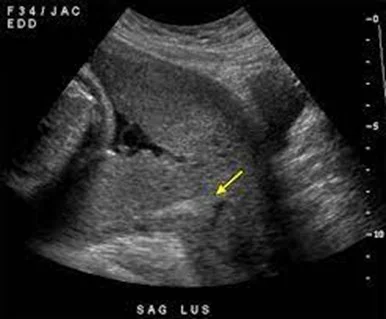

A presence of the placenta in the lower uterine segment, which can lead to partial or not full obstruction of the internal os.

- Ultrasound (Preferably Transvaginal) as patients will have been highlighted as having a low-lying placenta at their anomaly scan.